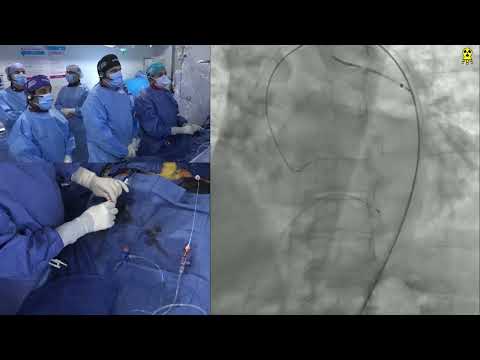

SAPIEN 3 TAVR (26mm) via Percutaneous Femoral Access - Structural Live Jan 2017

TAVR with 26mm SAPIEN 3 Ultra Valve via Right Femoral Percutaneous Approach

LIVE CASE 3 SAPIEN 3 TAVR with Difficult Vascular Access